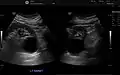

Advanced polycystic kidney disease with multiple cysts.[12]